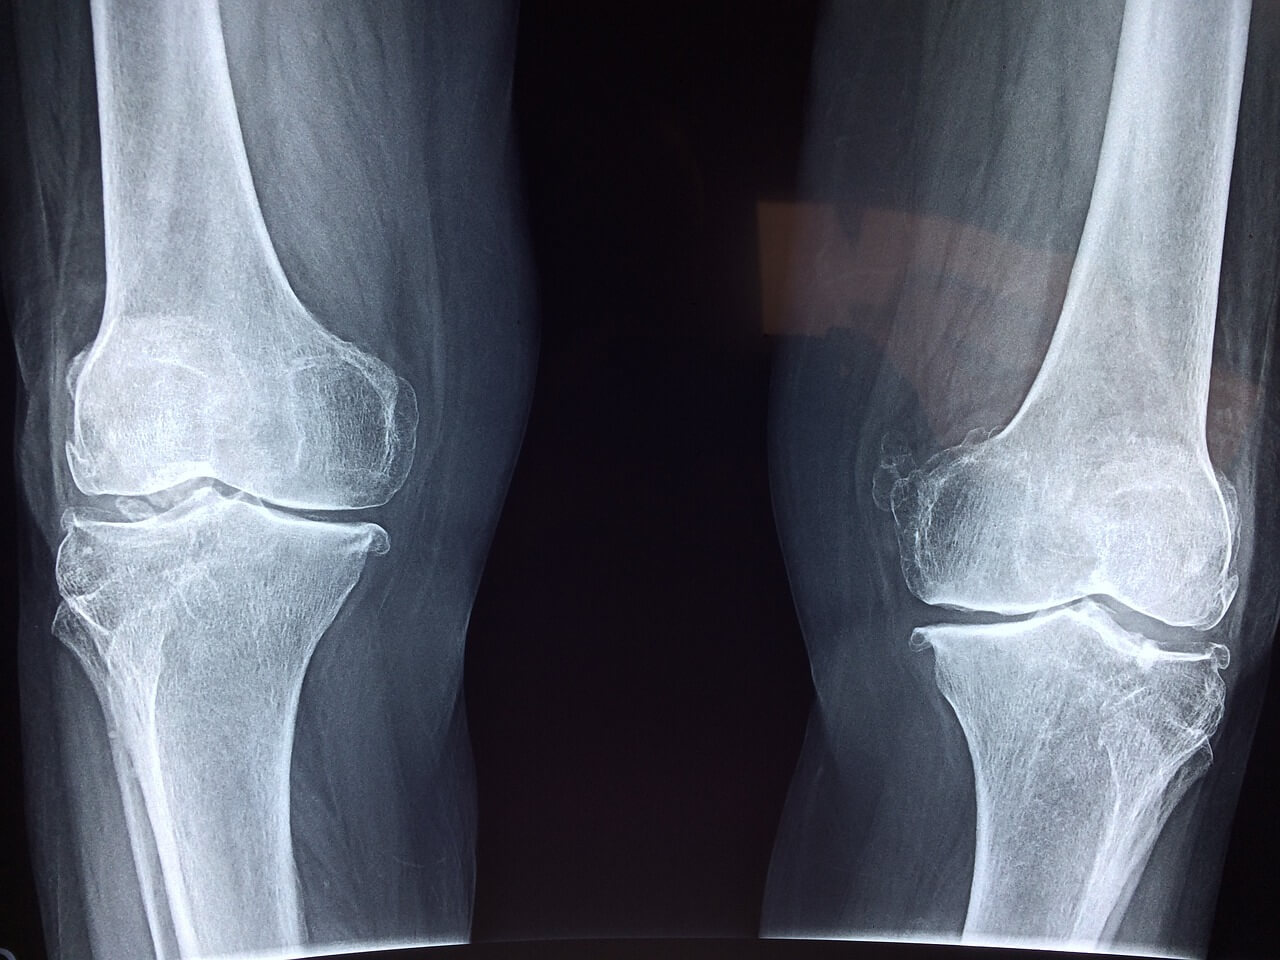

골다공증 초기증상은 눈에 잘 띄지 않아 많은 이들이 놓치기 쉽습니다. 뼈는 겉으로 드러나지 않지만 조용히 약해지고 있습니다. 사소한 허리 통증이나 무릎 불편감도 골다공증 초기증상일 수 있습니다.

골다공증 초기증상은 일상 속 사소한 불편으로 나타납니다. 무릎이 시큰거리거나 오래 서 있기가 힘들고, 이전보다 허리가 자주 아프다면 뼈 건강을 의심해봐야 합니다.

아침에 일어났을 때 뻣뻣함이 심하거나, 자세를 바꿀 때마다 뼈 마디가 욱신거리는 느낌도 골다공증 초기증상일 수 있습니다.